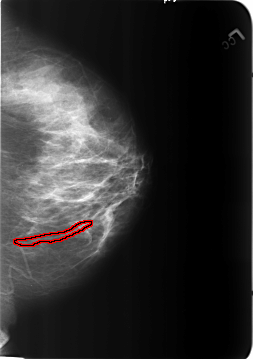

B_3212_1.LEFT_CC

FILE: B_3212_1.LEFT_CC.OVERLAY

TOTAL_ABNORMALITIES 1

ABNORMALITY 1

LESION_TYPE CALCIFICATION TYPE VASCULAR DISTRIBUTION N/A

ASSESSMENT 2

SUBTLETY 3

PATHOLOGY BENIGN_WITHOUT_CALLBACK

TOTAL_OUTLINES 1

BOUNDARY